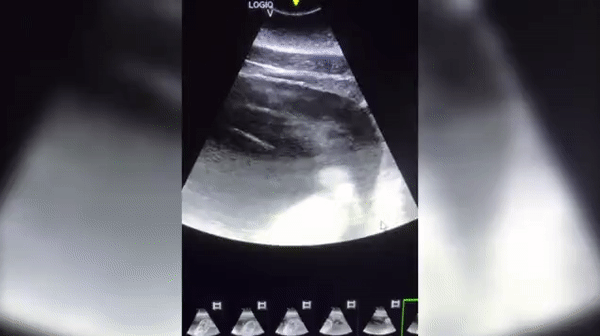

KSAT 등 현지매체 보도에 따르면, 텍사스주(州) 관광명소 ‘시월드 샌안토니오 지점’은 지난 11일(현지시간) 페이스북을 통해 암컷 벨루가 루나(Luna)의 배 속 태아를 촬영한 초음파 영상을 공개했다.

영상은 태아 상태의 새끼 벨루가가 움직일 때마다 그 머리와 눈 그리고 상반신 일부가 나타나는 모습을 담고 있다.

이에 대해 공원 측은 “어미는 ‘허즈번드리 트레이닝’(husbandry training)으로 불리는 특수 훈련을 받은 덕분에 수의팀이 검사하는 동안 가만히 있을 수 있어 초음파 영상을 기록할 수 있었다”고 설명했다. 허즈번드리 트레이닝은 동물원 등에서 멸종 위기에 처한 동물 등을 보존하기 위한 노력의 일부분으로 행하는 훈련 방법을 말한다.